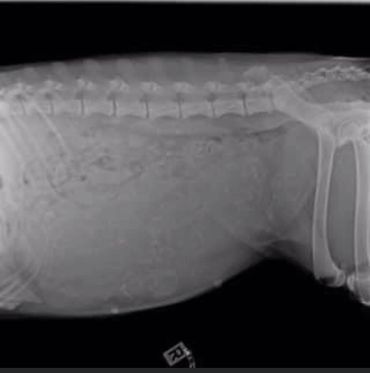

First time mom, Bobbay welcomed her litter of 9 beautiful puppies with a smooth delivery. With 7 girls and 2 boys, Bobbay took straight to motherhood and is a natural just like her mother Faith.